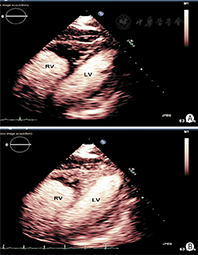

距离探头最近区域和聚焦区域的造影剂微泡破裂严重。如果是实时观察左室影像,由于气泡的破坏可观察到无造影剂增强或心尖区涡流。近场涡流成因是多因素的,主要成因是MI设置过高或注射造影剂剂量不足。通过及时注入新制备的造影剂进入心室腔补充或代替被破坏掉的造影剂的方法可以使涡流伪像消失;如果血流缓慢,新注入的造影剂未能及时充分替代被破坏的造影剂,则在流速最低的区域或高MI时,还会有涡流伪像。生理原因引起的心尖部血流速度超低(严重左心功能不全或心尖部大的室壁瘤)也是涡流伪像的常见原因(图1)。

是由于大量的造影剂充满在图像的近场及感兴趣区域。主要成因是单位时间内注射了过量的造影剂(注射速度太快或造影剂浓度太高)。随着时间的推移,造影剂在心室腔的浓度将渐渐减少,等待衰减伪像平息后即可继续获取图像。衰减还可能出现在左室胸骨旁长轴观切面,右室处造影剂气泡的破坏形成阴影笼罩在左室上方,影响了对左室的观察。心尖长轴切面的三腔心切面可以作为更好的观察切面。